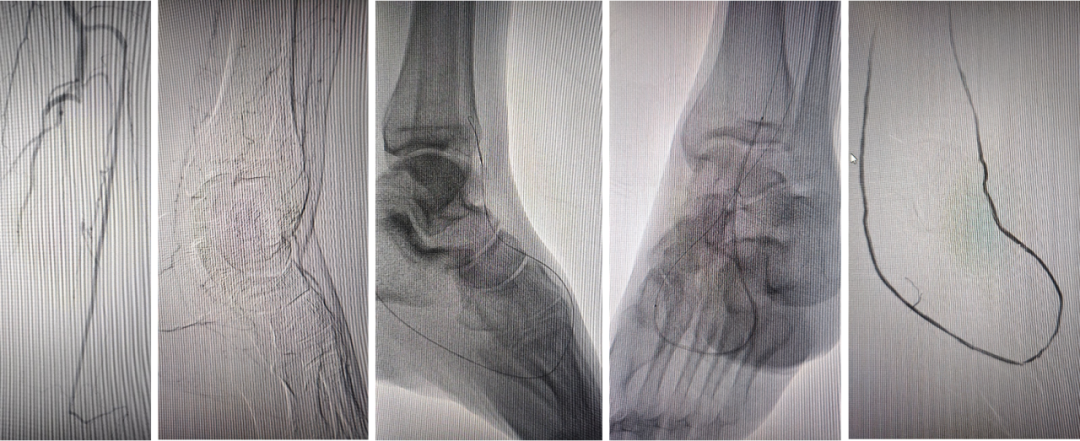

★ 第一足趾感染迁延不愈

Case 7:老年男性患者,第一足趾感染持续不愈达三月余。造影显示胫前动脉远端闭塞,胫后动脉缺如,腓动脉侧支供血不良。术者通过足弓将导丝送入第一足趾动脉,以1.5mm及2.0mm球囊逐级扩张。术后不足一月溃疡愈合,虽三个月后血管再闭塞,但感染未复发,随访两年稳定。

★ 年轻糖足合并脉管炎

Case 8:30岁左右糖尿病患者,三支膝下动脉闭塞,远端足底无流出道。经胫后动脉逆向开通后,足背动脉为腓动脉延续的变异,足趾动脉完全缺失。术中被迫将导丝逐一送入3-4支足趾动脉,用2.0mm球囊扩张,术后造影虽血流缓慢,但足弓显影改善。开通维持约半年。